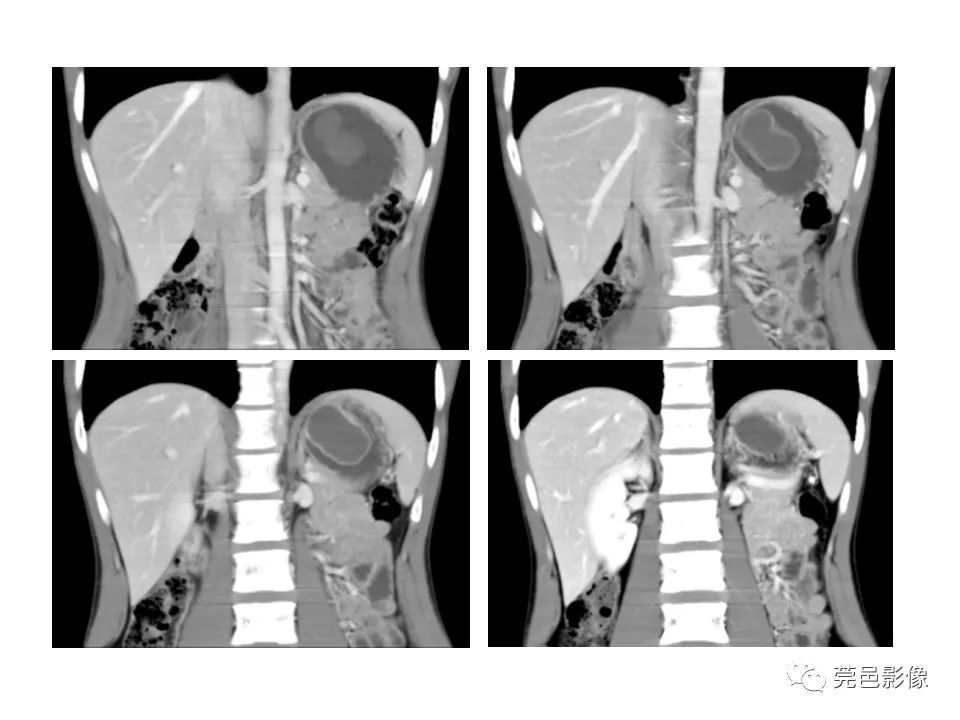

畸形|胃重复畸形CT诊断与鉴别诊断

【 畸形|胃重复畸形CT诊断与鉴别诊断】